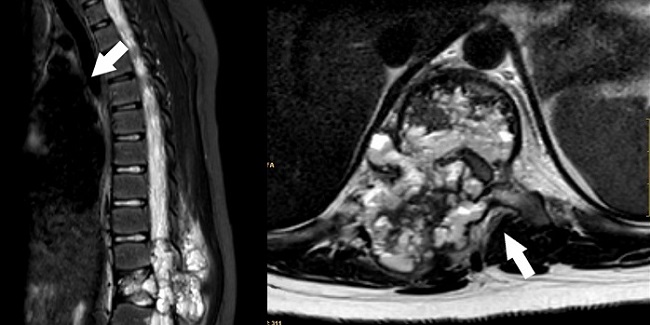

El segundo caso es una mujer de 10 años que consulta por dolor lumbar de predominio nocturno de 4 meses de evolución. No impotencia funcional para la deambulación ni otra sintomatología. A la exploración física, actitud escoliótica por dolor lumbar con leve edema a nivel de L2-L3, resto normal. Ante lumbalgia con datos de alarma (dolor nocturno), se realizan radiografía ósea (Fig. 3) y RM (Figs. 4 y 5) donde se aprecia lesión osteolítica expansiva con nivel líquido en su interior en arco posterior izquierdo de L3, así como edema de médula ósea y partes blandas y tomografía computarizada (TC; Fig. 6) donde se describe lesión lobulada y con margen esclerótico, planteando el mismo diagnóstico diferencial que en el caso anterior. Se realiza resección en bloque de la lesión y se confirma histológicamente el diagnóstico de QOA. Actualmente se encuentra sin clínica y recuperada.